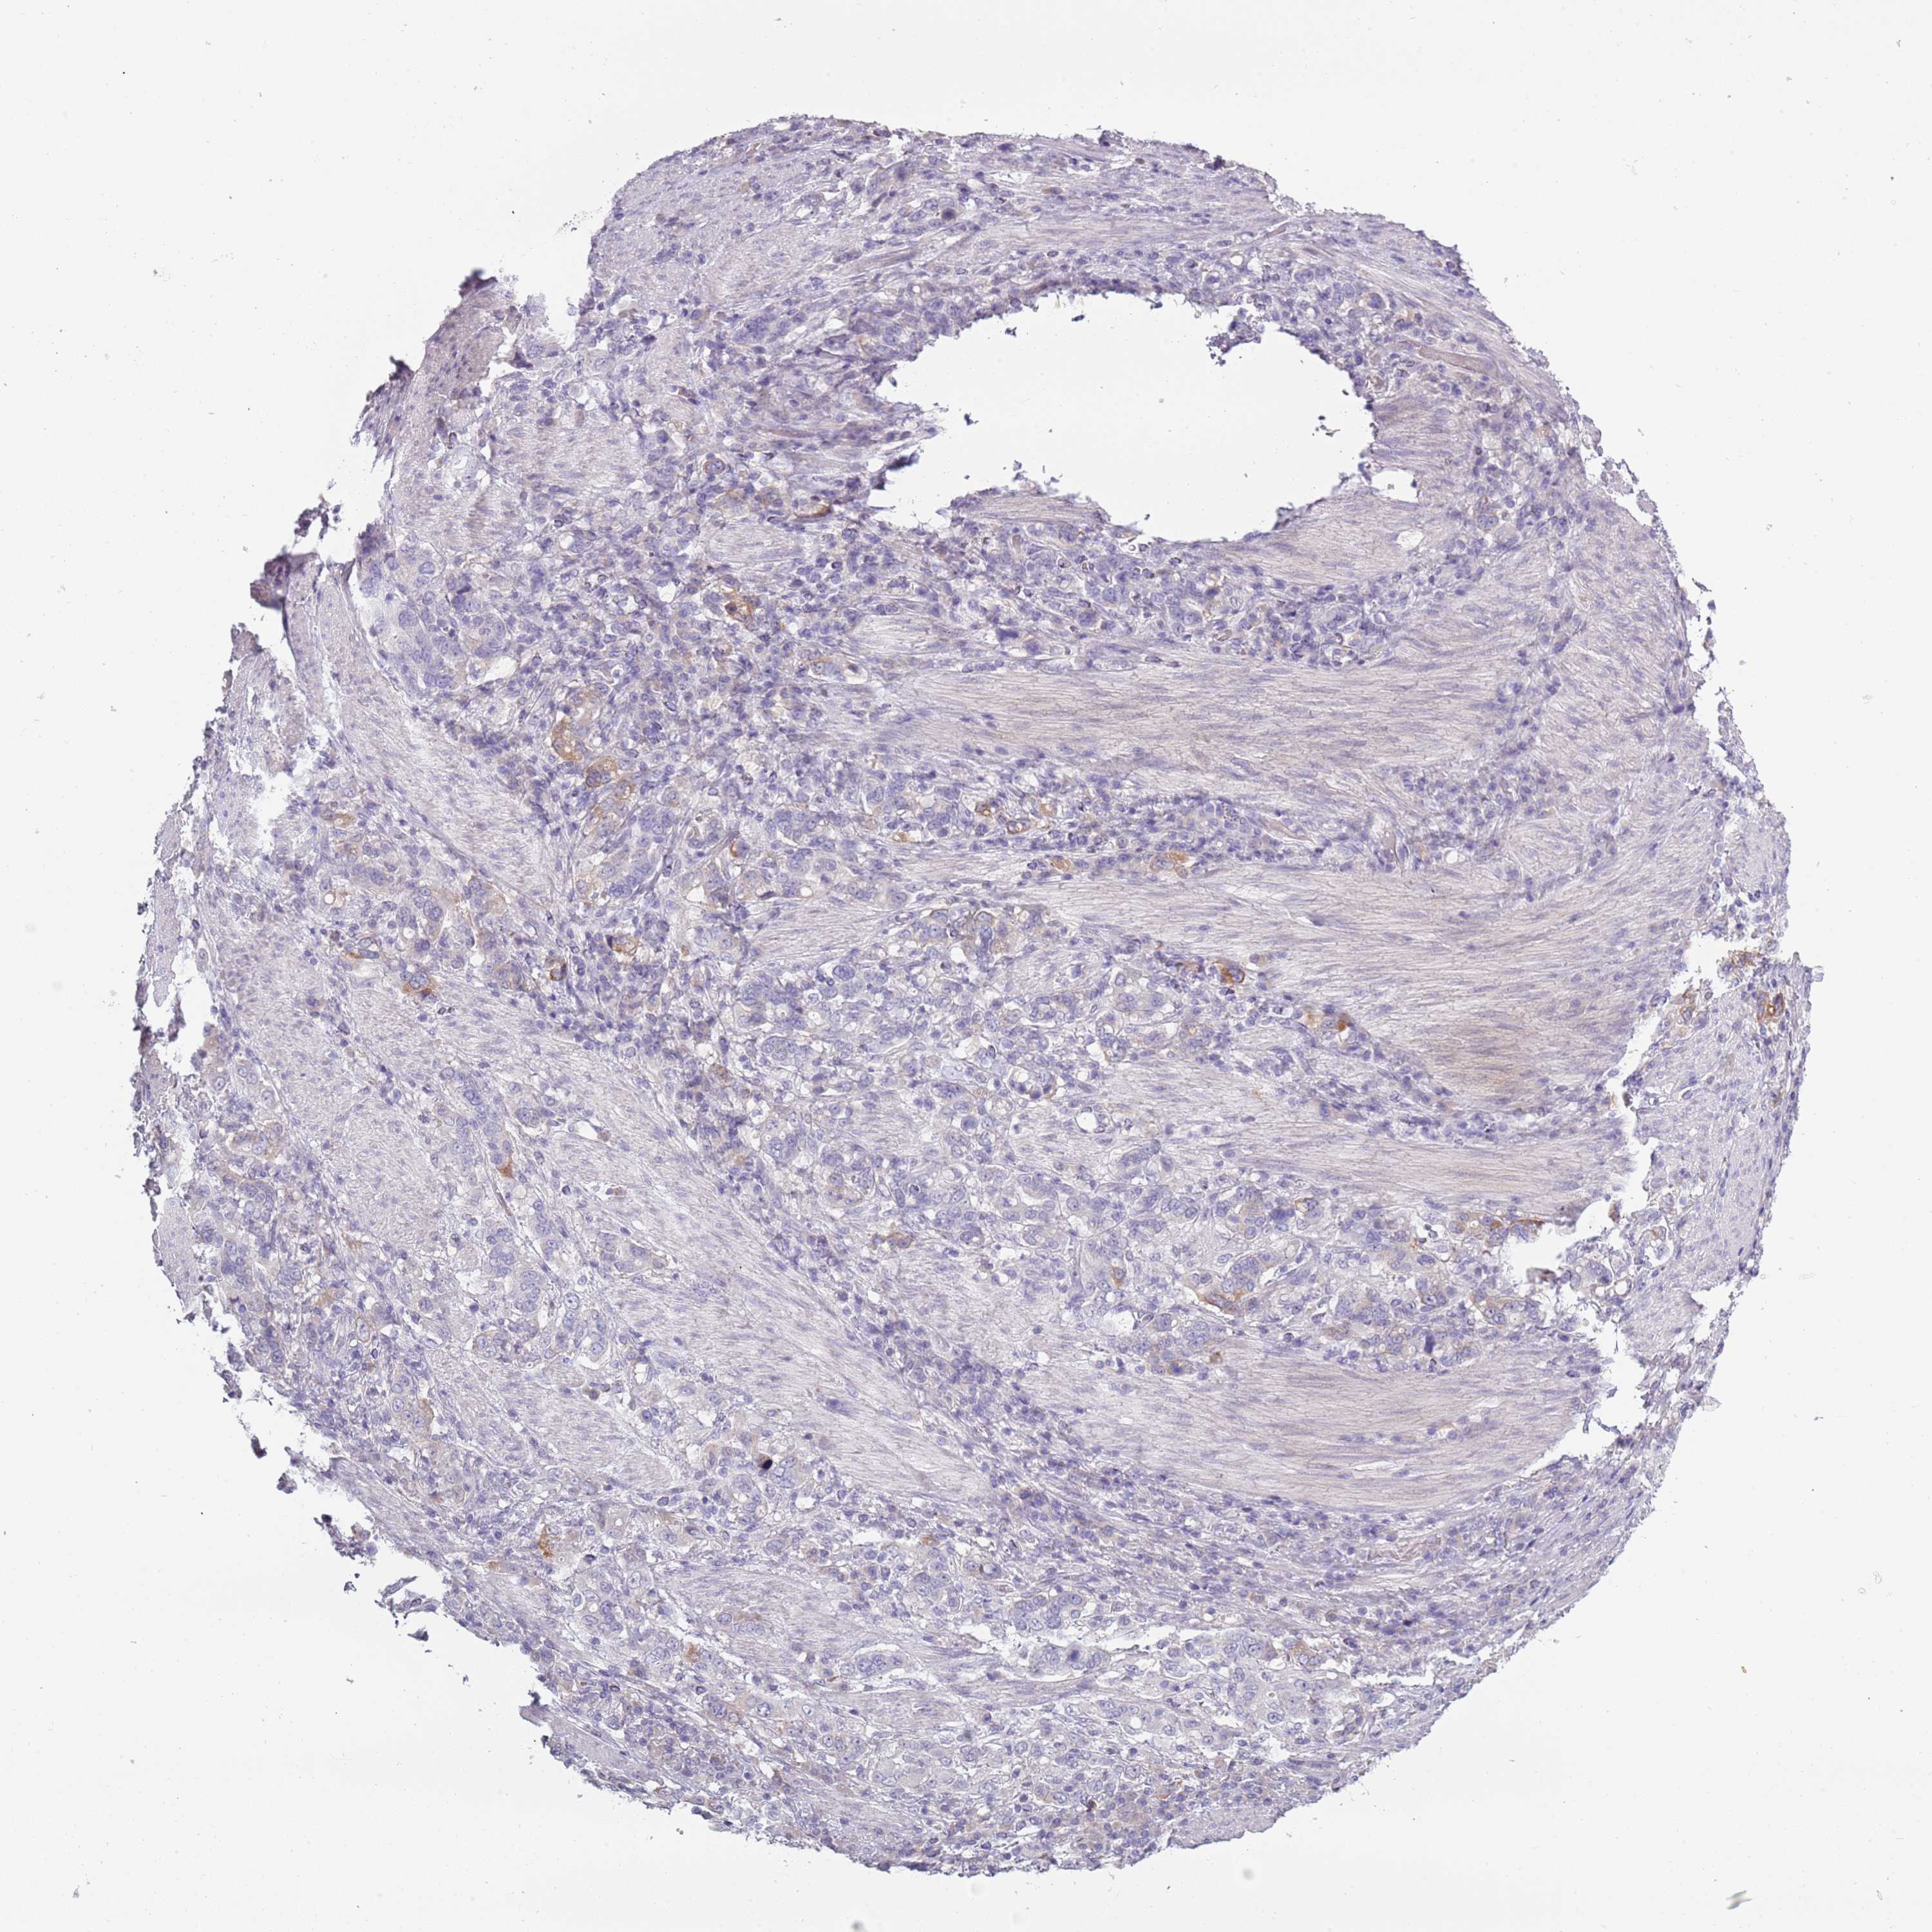

STOMACH CANCER - Protein expressioni

A mouse-over function shows sample information and annotation data. Click on an image to view it in a full screen mode. Samples can be filtered based on level of antibody staining by selecting one or several of the following categories: high, medium, low and not detected. The assay and annotation is described here.

Note that samples used for immunohistochemistry by the Human Protein Atlas do not correspond to samples in the TCGA dataset.

Antibody stainingi

Antibody staining in the annotated cell types in the current human tissue is reported as not detected, low, medium, or high, based on conventional immunohistochemistry profiling in selected tissues. This score is based on the combination of the staining intensity and fraction of stained cells.

Each image is clickable and will lead to virtual microscopy that enables deeper exploration of all samples and also displays staining intensity scores, fraction scores and subcellular localization as well as patient and tissue information for each sample.

Antibody HPA047154

Staining

High

Medium

Low

Not detected

Intensity

Strong

Moderate

Weak

Negative

Quantity

>75%

75%-25%

<25%

None

Location

Nuclear

Cytoplasmic/membranous

Cytoplasmic/membranous,nuclear

Adenocarcinoma, NOS